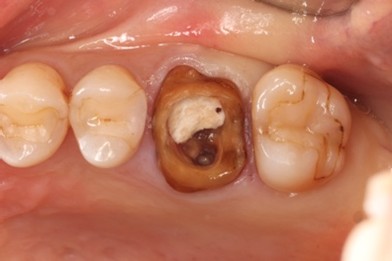

Before

抜歯およびRidge Preservation時の口腔内写真

抜歯時に頬側の骨の大きな欠損を認めた。サイトランス®を使用したRidge Preservation、Cytoplast®※を使用し抜歯窩を被覆

骨の再生が起きており十分な骨幅を認める

補綴後の口腔内写真

他院で歯が割れていると診断され、インプラントを勧められました

マイクロスコープにて歯の破折を確認し、患者さんとも相談の上、抜歯しインプラント埋入となった

破折歯を抜歯した場合、今回のケースのように骨の吸収が著しく生じていることが多く、このままではインプラント周囲に十分な骨幅(理想的にはプラットフォームから2mmの骨幅)を維持することができないためRidge Preservationは非常に有効な手法であると考える。